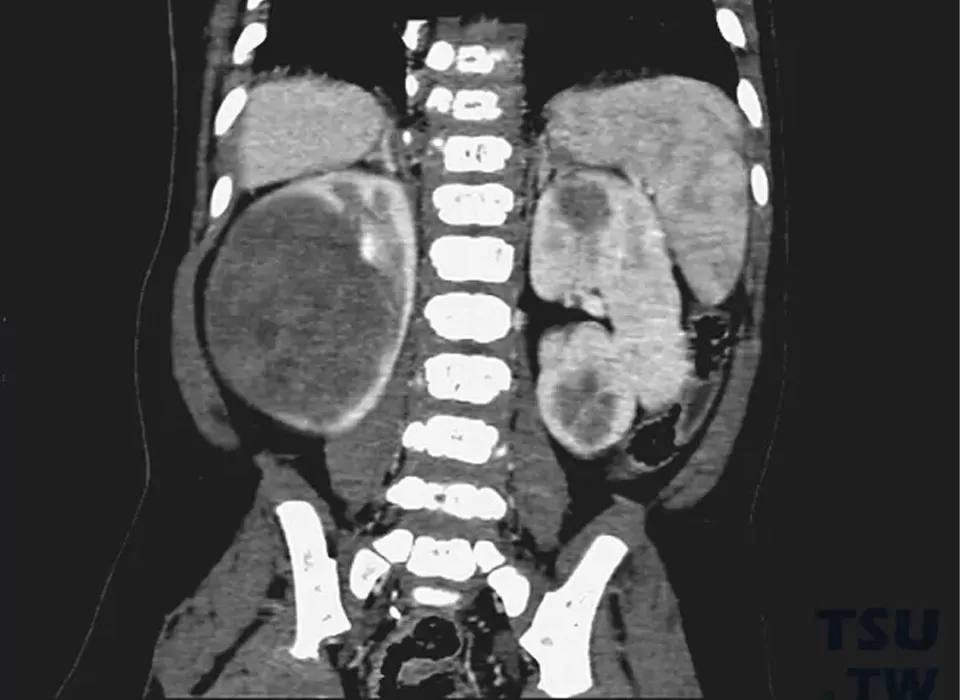

2. Imaging Dawn (1960-1980): Intravenous pyelography combined with ultrasound examination, increasing detection rate to 89%

A deep learning system developed by Japan's National Cancer Center can distinguish Wilms tumor from other renal claw sign wilms tumor by analyzing texture features (entropy > 6.5, contrast < 45) in enhanced CT images, with an accuracy of 97%. The preoperative chemotherapy response evaluation system established by the International Society of Pediatric Oncology (SIOP) increased the complete surgical resection rate from 68% to 92%.